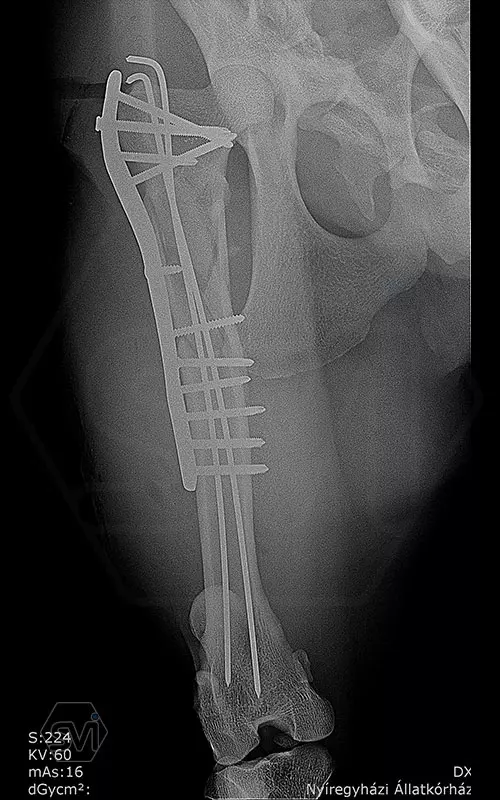

The 9-year-old female cheetah broke her leg so miserably near the femoral neck during a regrouping. Here again, the combination of the intramedullary pin and polyaxial lockin plate mentioned in the previous post was used to fix the fracture. During the screw insertions into the proximal piece, the polyaxiality came in really handy, we were able to avoid the 2.5 mm K-nails with the long screws. I hope the 14-hole 12 * 4 mm wide polyaxial plate (which could have been longer…) will be long enough, with a mix of 4.0 and 3.5 mm screws for maximum stability. From below, screw 6 is a cortical screw that secures a larger contralateral fragment as a lag screw.

Thus, 3 screws of different thicknesses (3.5 and 4.0 polyaxes) and shapes (AO screws) were placed in the plate, while ONE screwdriver was used because each has a hex head.